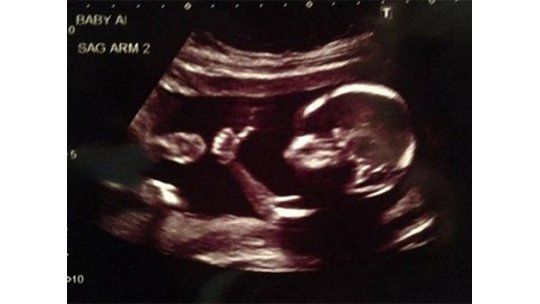

Increíble el bebé que saluda a sus padres en las ecografías

En la imagen se ve al bebé levantando el pulgar como para que sus progenitores confirmen que está todo bien.

Una ecografía realmente sorprendente es la de este bebé que levanta el dedo pulgar como a modo de confirmar a sus padres que se encuentra en excelente estado.

La imagen fue captada por el padre mientras el médico revisaba cómo seguía el embarazo, detalla Infobae.

El niño nacerá en enero y aún no conocen el sexo.

Si bien en las redes sociales algunos mostraron escepticismo sobre la veracidad de la foto, el padre, que usa el apodo de "meancloth", remarcó que es real y fue tomada el pasado 27 de agosto.

Foto: Meancloth